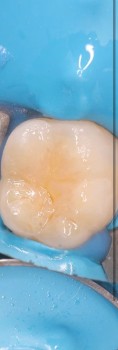

4 работы в портфолио